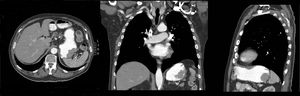

Varón de 79 años con antecedentes de melanoma en brazo izquierdo 3 años antes, tratado con cirugía y radioterapia, que es diagnosticado de adenocarcinoma de colon. En el estudio de extensión se objetiva la presencia de una lesión polipoidea de crecimiento predominantemente endoluminal en fundus gástrico de unos 5cm de diámetro sin signos aparentes de extensión transmural ni adenopatías regionales (fig. 1). Se realizó gastroscopia que confirmó la presencia de una lesión polipoidea en fundus, de unos 5cm, con áreas ulceradas e irregulares, sugestiva de malignidad (fig. 2), siendo la biopsia compatible con metástasis por melanoma. Se realizó hemicolectomía derecha laparoscópica más gastrectomía atípica.